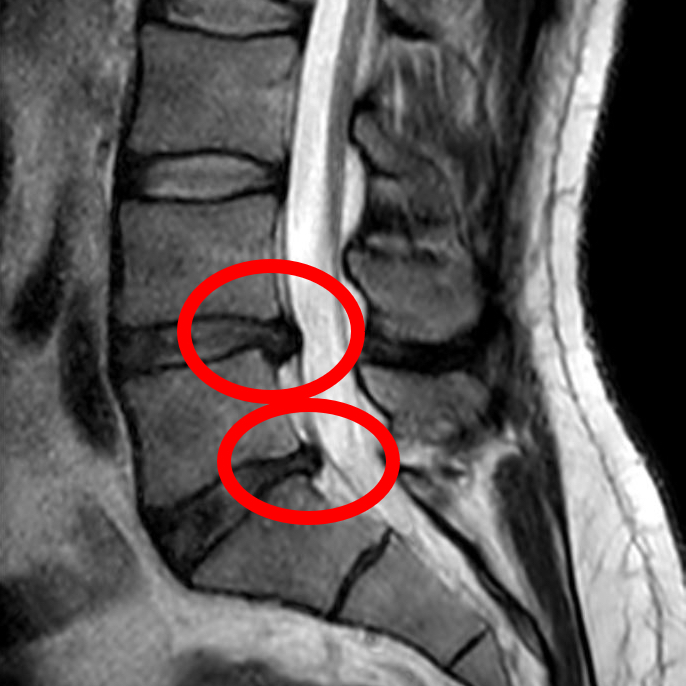

THE MRI PARADOX

You Are Not Your Scan

In Singapore, patients are often terrified by MRI reports mentioning “Slipped Discs” or “Degeneration.” However, large-scale studies show these are often normal age-related changes, even in people with zero pain. As your Singapore chiropractor, we focus on function, not scans.

- •

Spontaneous Resorption: Research shows up to 66% of disc herniations heal and “shrink” naturally over time. - •

The “Grey Hair” Effect: Disc bulges are as common as grey hair or wrinkles—they don’t automatically mean you will have pain. - •

Function > Structure: Recovery is driven by restoring how your spine functions, not by fixing a picture on a scan.

The Clinical Truth

Unnecessary MRIs lead to worse outcomes and higher surgery rates. Focus on building a “spinal brace” through movement for healthier spinal discs and joints.